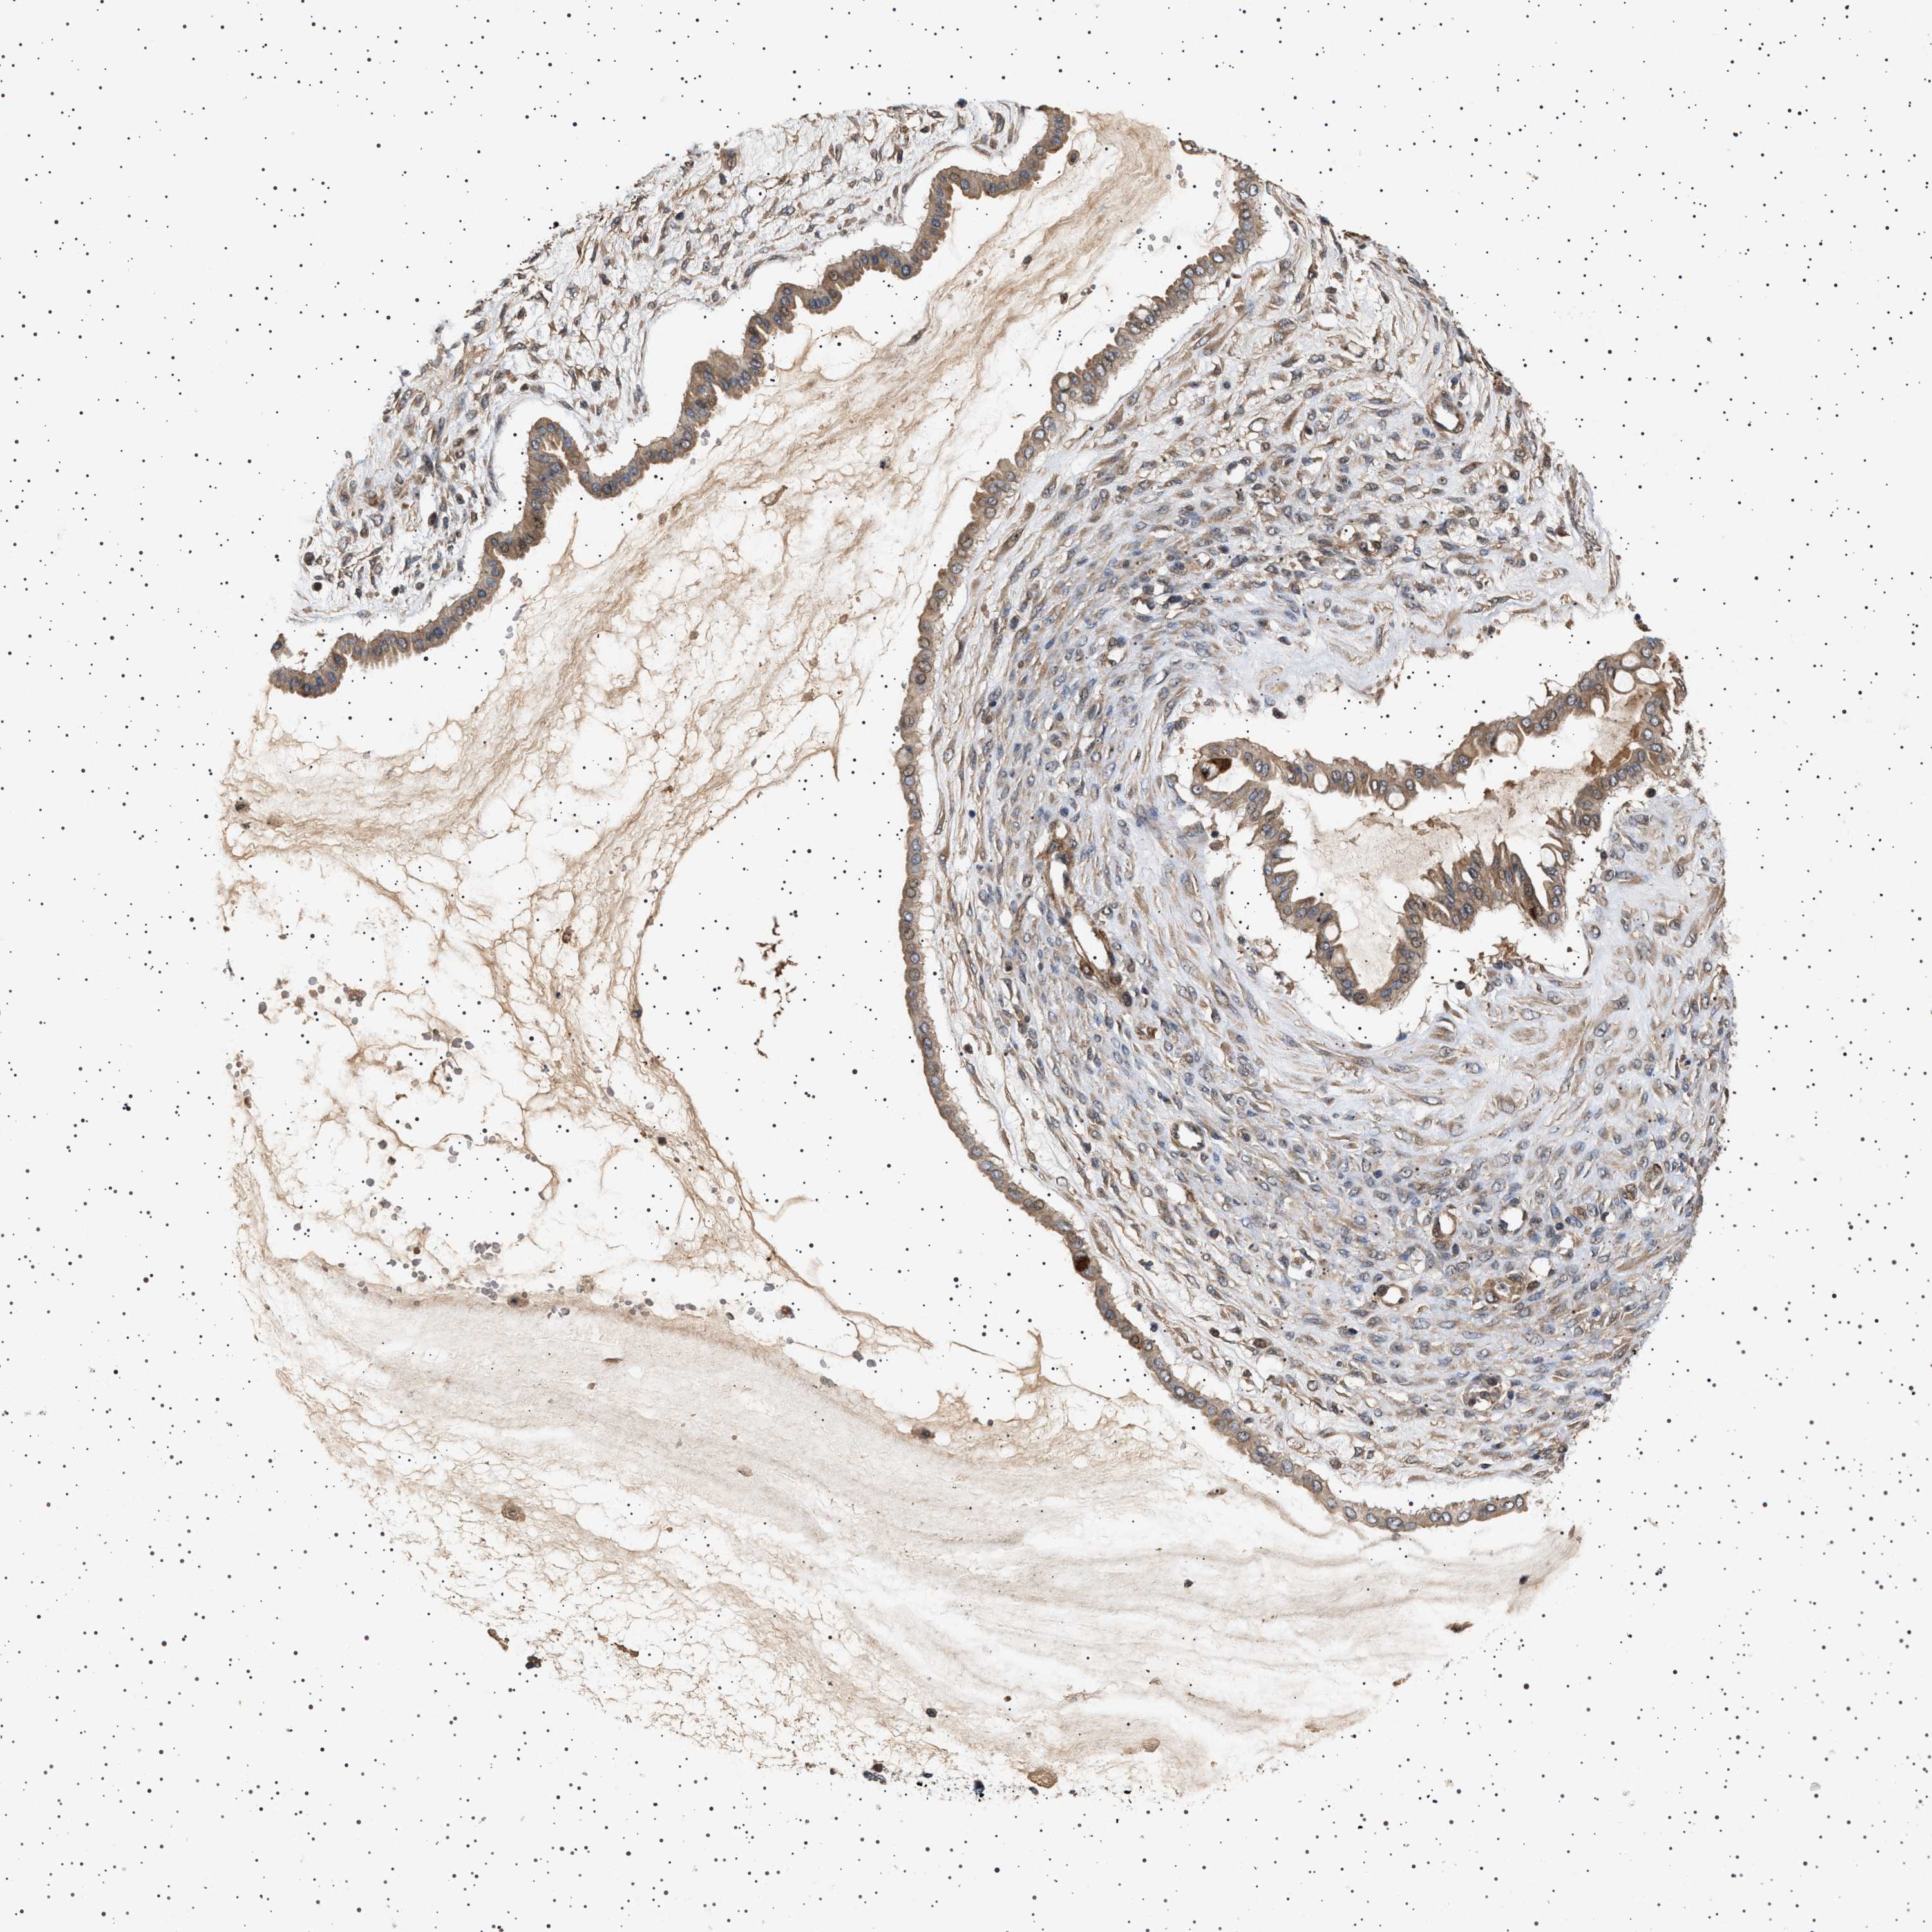

OVARIAN CANCER - Protein expressioni

A mouse-over function shows sample information and annotation data. Click on an image to view it in a full screen mode. Samples can be filtered based on level of antibody staining by selecting one or several of the following categories: high, medium, low and not detected. The assay and annotation is described here.

Note that samples used for immunohistochemistry by the Human Protein Atlas do not correspond to samples in the TCGA dataset.

Antibody stainingi

Antibody staining in the annotated cell types in the current human tissue is reported as not detected, low, medium, or high, based on conventional immunohistochemistry profiling in selected tissues. This score is based on the combination of the staining intensity and fraction of stained cells.

Each image is clickable and will lead to virtual microscopy that enables deeper exploration of all samples and also displays staining intensity scores, fraction scores and subcellular localization as well as patient and tissue information for each sample.

Antibody HPA020870

Antibody CAB010890

Cystadenocarcinoma, serous, NOS